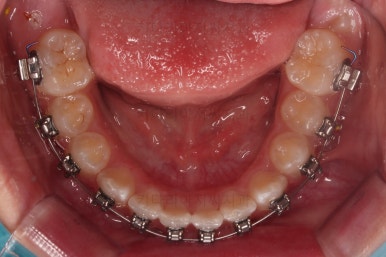

아랫니도 바로 교정장치를 부착하고, 교정장치를 통해 윗니~아랫니를 끌어주고 철사를 이리저리 디자인해서 힘을 주고, 다양한 부가적인 부착물들을 활용하기로 했어요.

어떤 장치가 중간중간 활용되고 있는지는 틀린그림찾기처럼 찾아보시길 바랍니다.ㅎㅎ

과개교합, 옥니, 앵글씨 2급 부정교합 모두 좋아지고 있어요.

마무리를 해줍니다.

앞니 각도가 매우 좋아졌고요.(옥니 개선) 위 아래 앞니가 덮는 정도도 개선되었어요.(과개교합, 딥바이트)

엉성했던 어금니 맞물림도 매우 좋아졌어요.(앵글씨 2급 부정교합)